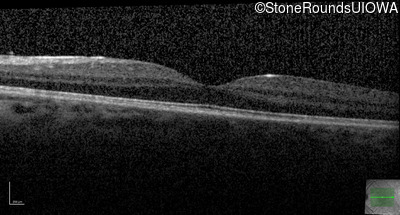

Optical Coherence Tomography - Left - 20/20 -1

Exemplar / OCT Stack